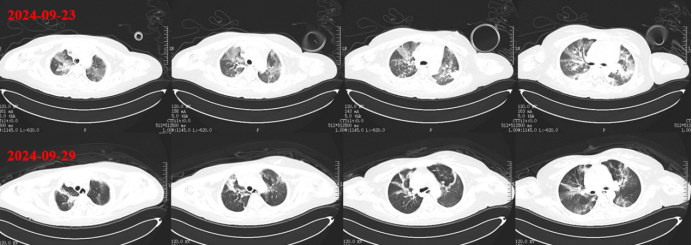

928日外出复查胸部CT:双肺渗出和实变明显吸收改善(图10,图11)

图片

10  复查胸部CT(2024-09-29)

11  患者胸部CT对比